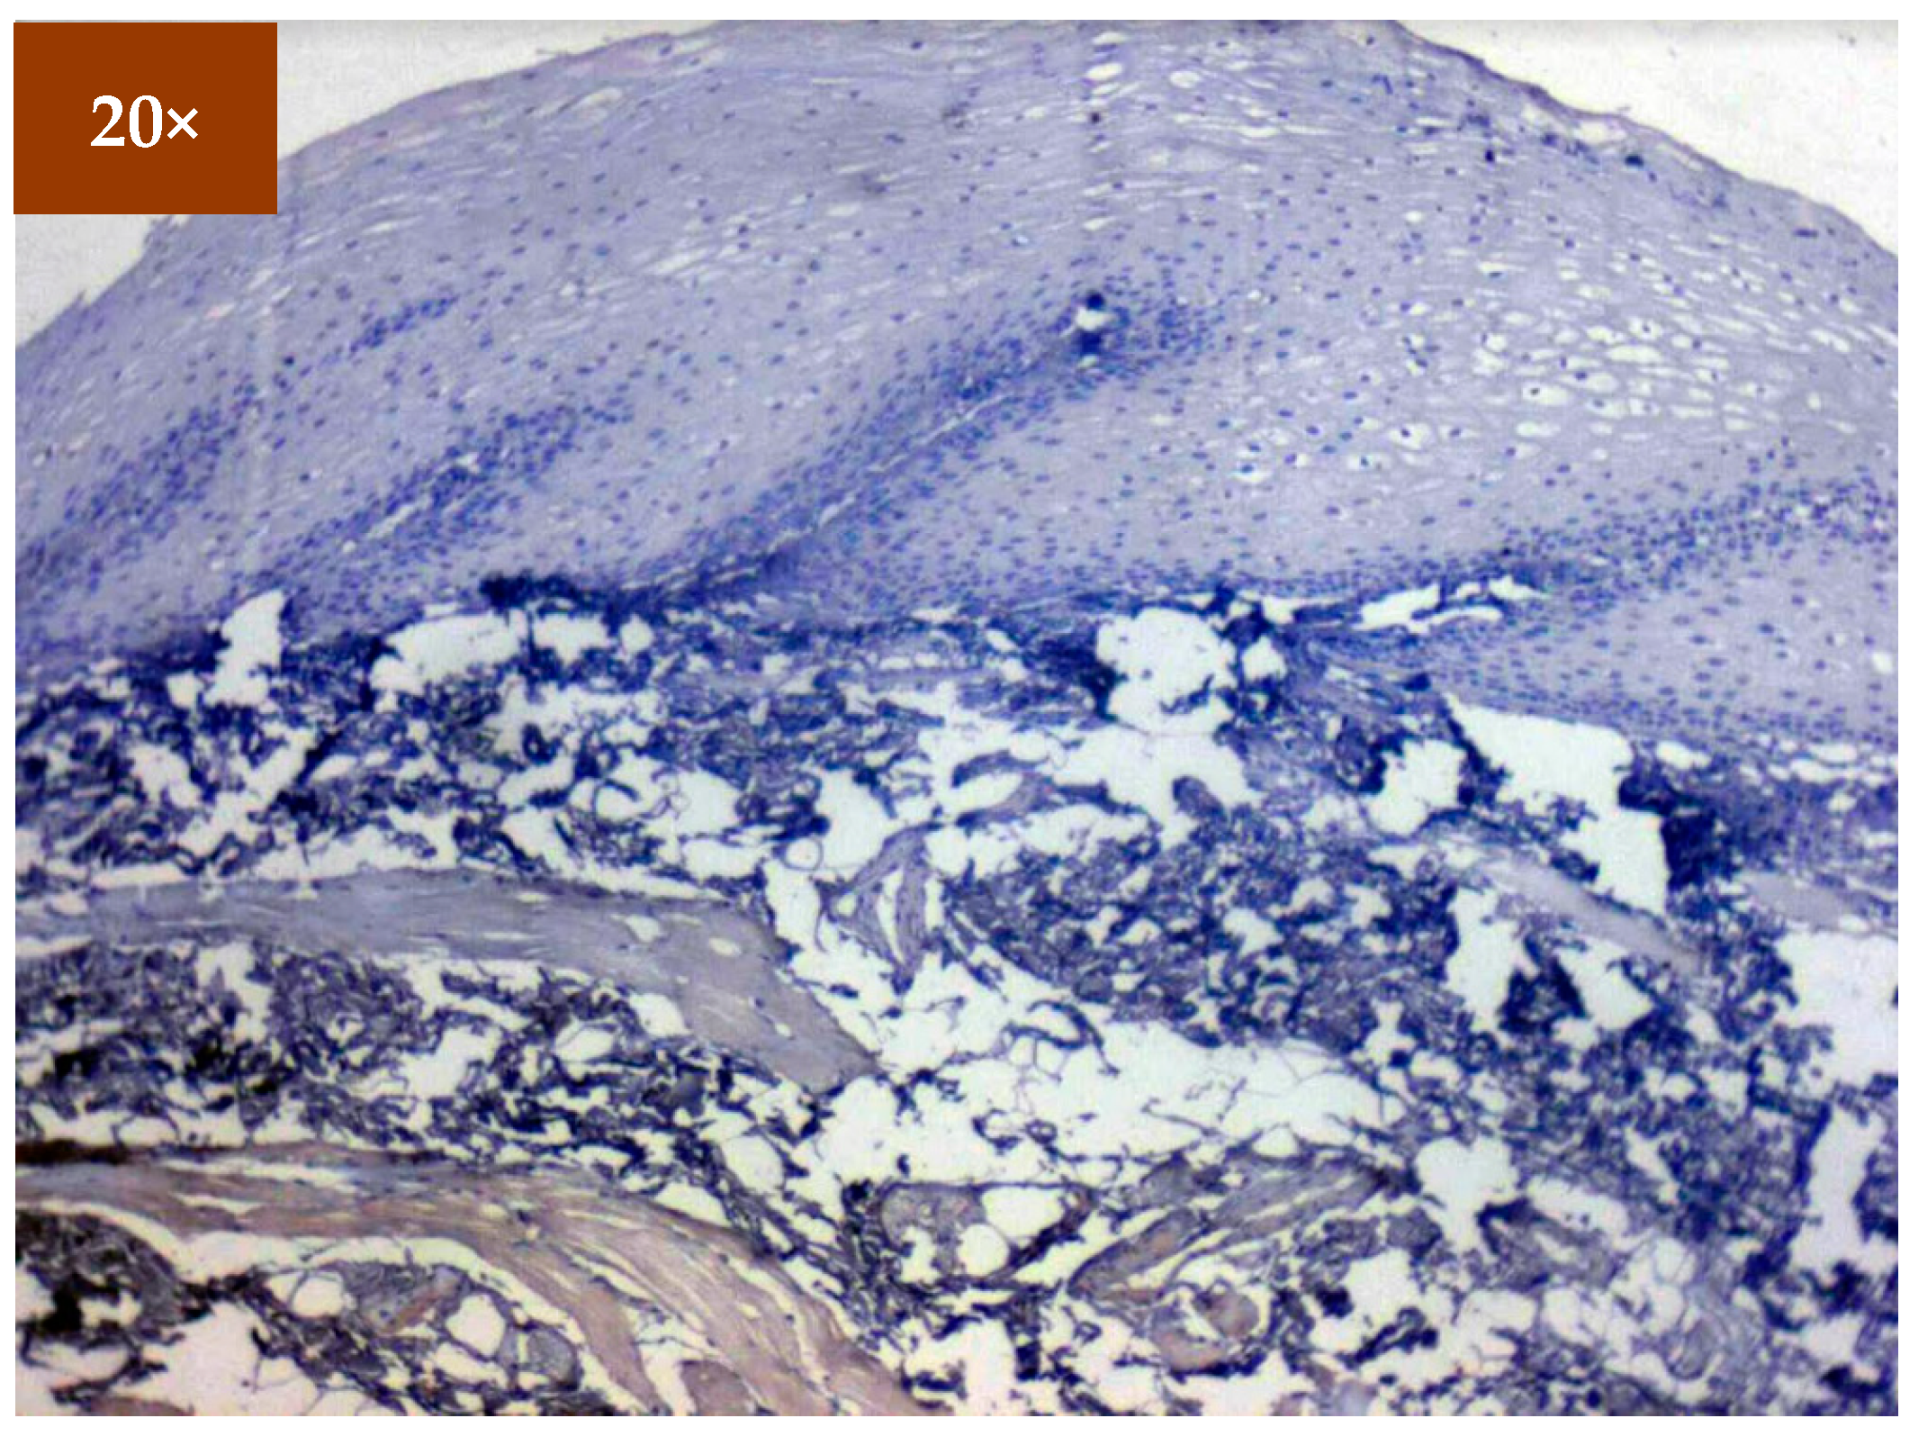

3.2. Immunohistochemistry

Expression of EGFR was studied in 173 patients in different age groups, in which mild positive immunoexpression was found in 23 patients (13.3%), intermediate positive immunoexpression was found in 51 patients (29.5%), strong positive immunoexpression was found in 87 patients (50.3%), and 12 patients (6.9%) tested negative (Table 2). EGFR overexpression was increased in oral cancer and OSMF compared to healthy controls (p = 0.000; χ2 = 68.620). EGFR overexpression was significantly correlated (p = 0.000; χ2 = 85.409) with various grades of dysplasia, and well-differentiated (WDSCC) and moderately differentiated squamous cell carcinoma (MDSCC) (Table 3). Figure 3 shows the expression of EGFR in healthy controls showing negative expression. Figure 4 shows the expression of EGFR in OSMF, showing intense cytoplasmic and nuclear positivity. Figure 5 and Figure 6 show the expression of EGFR in dysplasia and OSCC samples, respectively, showing intense cytoplasmic and nuclear positivity.

Figure 3.

IHC for EGFR in healthy controls (under 20× magnification).

Figure 4.

IHC of EGFR in OSMF samples (under 20× magnification).